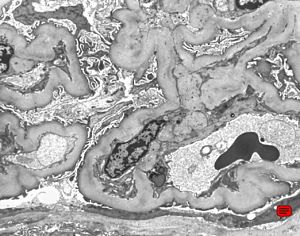

M,17y. | Alport syndrome - split and laminated basement membranes

F,14y. | Alport syndrome - split and laminated, thick/thin basement membranes